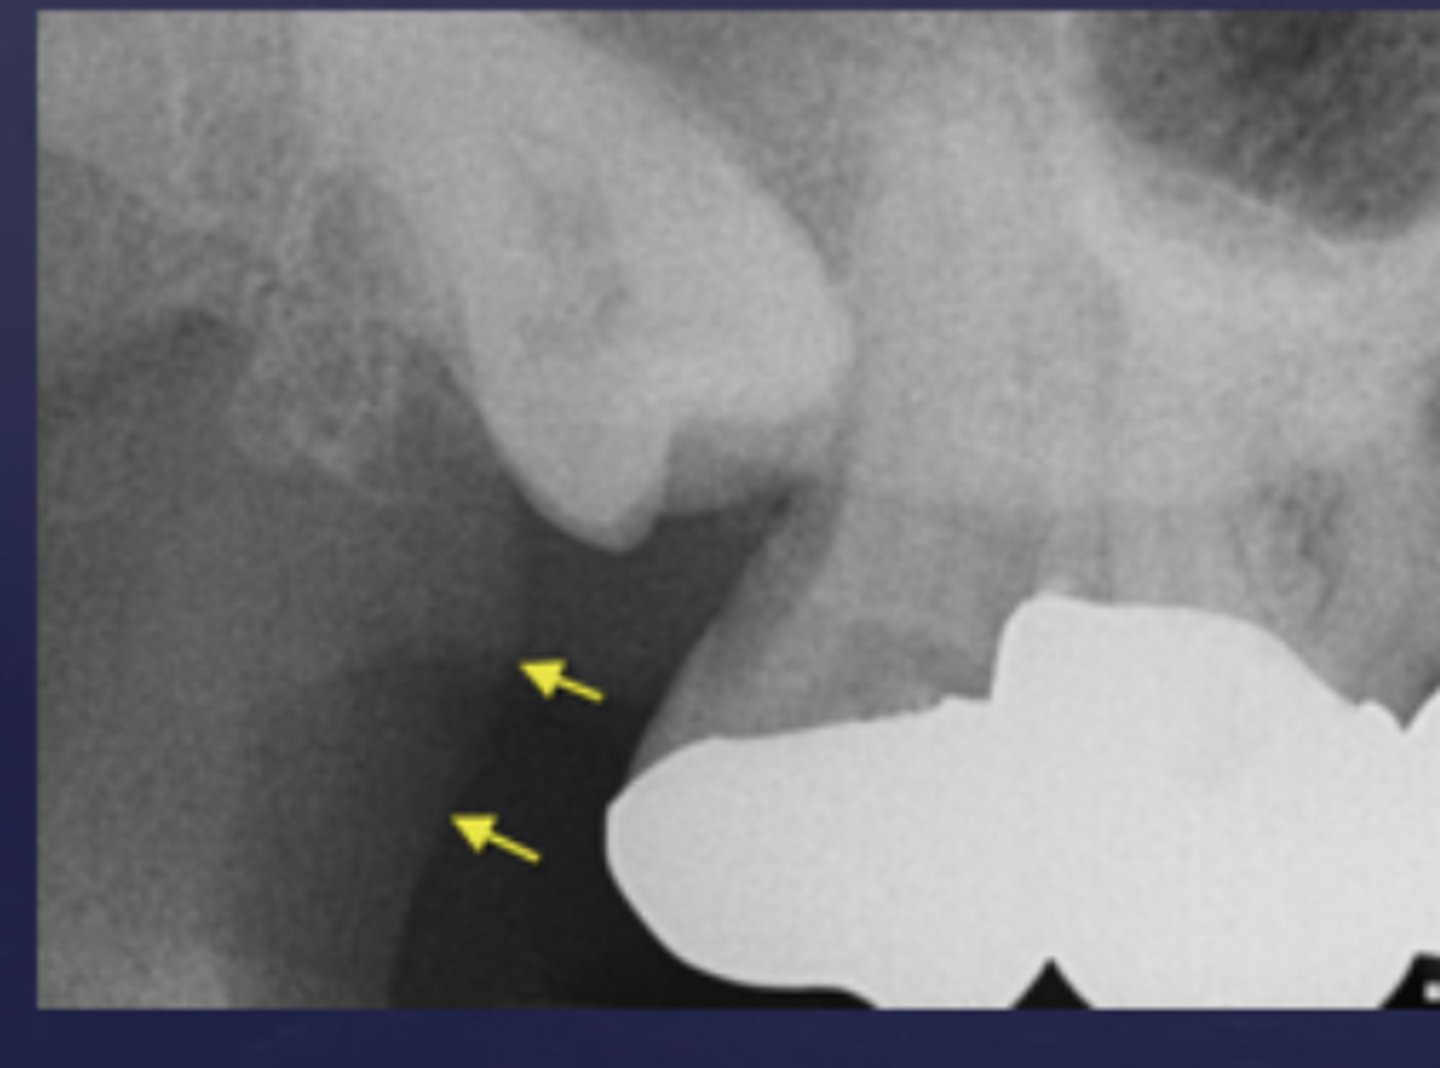

mandibular canal

border on top and bottom by a white line

passageway for nerves and blood vessels